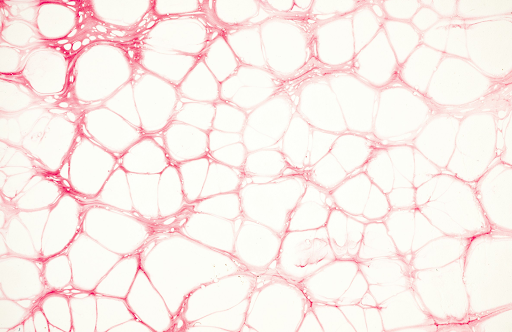

Experience the wonders of non-fractional, non-ablative laser technology , a scientifically advanced laser skin treatment that renews your skin without damaging or removing its outer layer. Instead, targeted thermal energy gently penetrates the dermal layers to stimulate natural collagen production - renewing the skin from the inside out. With this innovative laser technology, you can now embrace a non-invasive alternative for wrinkle reduction, free from any pain, redness, and downtime. With no impact on melanin in the skin, this technology is also safe for all skin types.